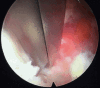

Surgical treatment of the degenerative disc disease has evolved from traditional open spine surgery to minimally invasive spine surgery including endoscopic spine surgery. Constant improvement in the imaging modality especially with introduction of the magnetic resonance imaging, it is possible to identify culprit degenerated disc segment and again with the discography it is possible to diagnose the pain generator and pathological degenerated disc very precisely and its treatment with minimally invasive approach. With improvements in the optics, high resolution camera, light source, high speed burr, irrigation pump etc, minimally invasive spine surgeries can be performed with various endoscopic techniques for lumbar, cervical and thoracic regions. Advantages of endoscopic spine surgeries are less tissue dissection and muscle trauma, reduced blood loss, less damage to the epidural blood supply and consequent epidural fibrosis and scarring, reduced hospital stay, early functional recovery and improvement in the quality of life & better cosmesis. With precise indication, proper diagnosis and good training, the endoscopic spine surgery can give equally good result as open spine surgery. Initially, endoscopic technique was restricted to the lumbar region but now it also can be used for cervical and thoracic disc herniations. Previously endoscopy was used for disc herniations which were contained without migration but now days it is used for highly up and down migrated disc herniations as well. Use of endoscopic technique in lumbar region was restricted to disc herniations but gradually it is also used for spinal canal stenosis and endoscopic assisted fusion surgeries. Endoscopic spine surgery can play important role in the treatment of adolescent disc herniations especially for the persons who engage in the competitive sports and the athletes where less tissue trauma, cosmesis and early functional recovery is desirable. From simple chemonucleolysis to current day endoscopic procedures the history of minimally invasive spine surgery is interesting. Appropriate indications, clear imaging prior to surgery and preplanning are keys to successful outcome. In this article basic procedures of percutaneous endoscopic lumbar discectomy through transforaminal and interlaminar routes, percutaneous endoscopic cervical discectomy, percutaneous endoscopic posterior cervical foraminotomy and percutaneous endoscopic thoracic discectomy are discussed.